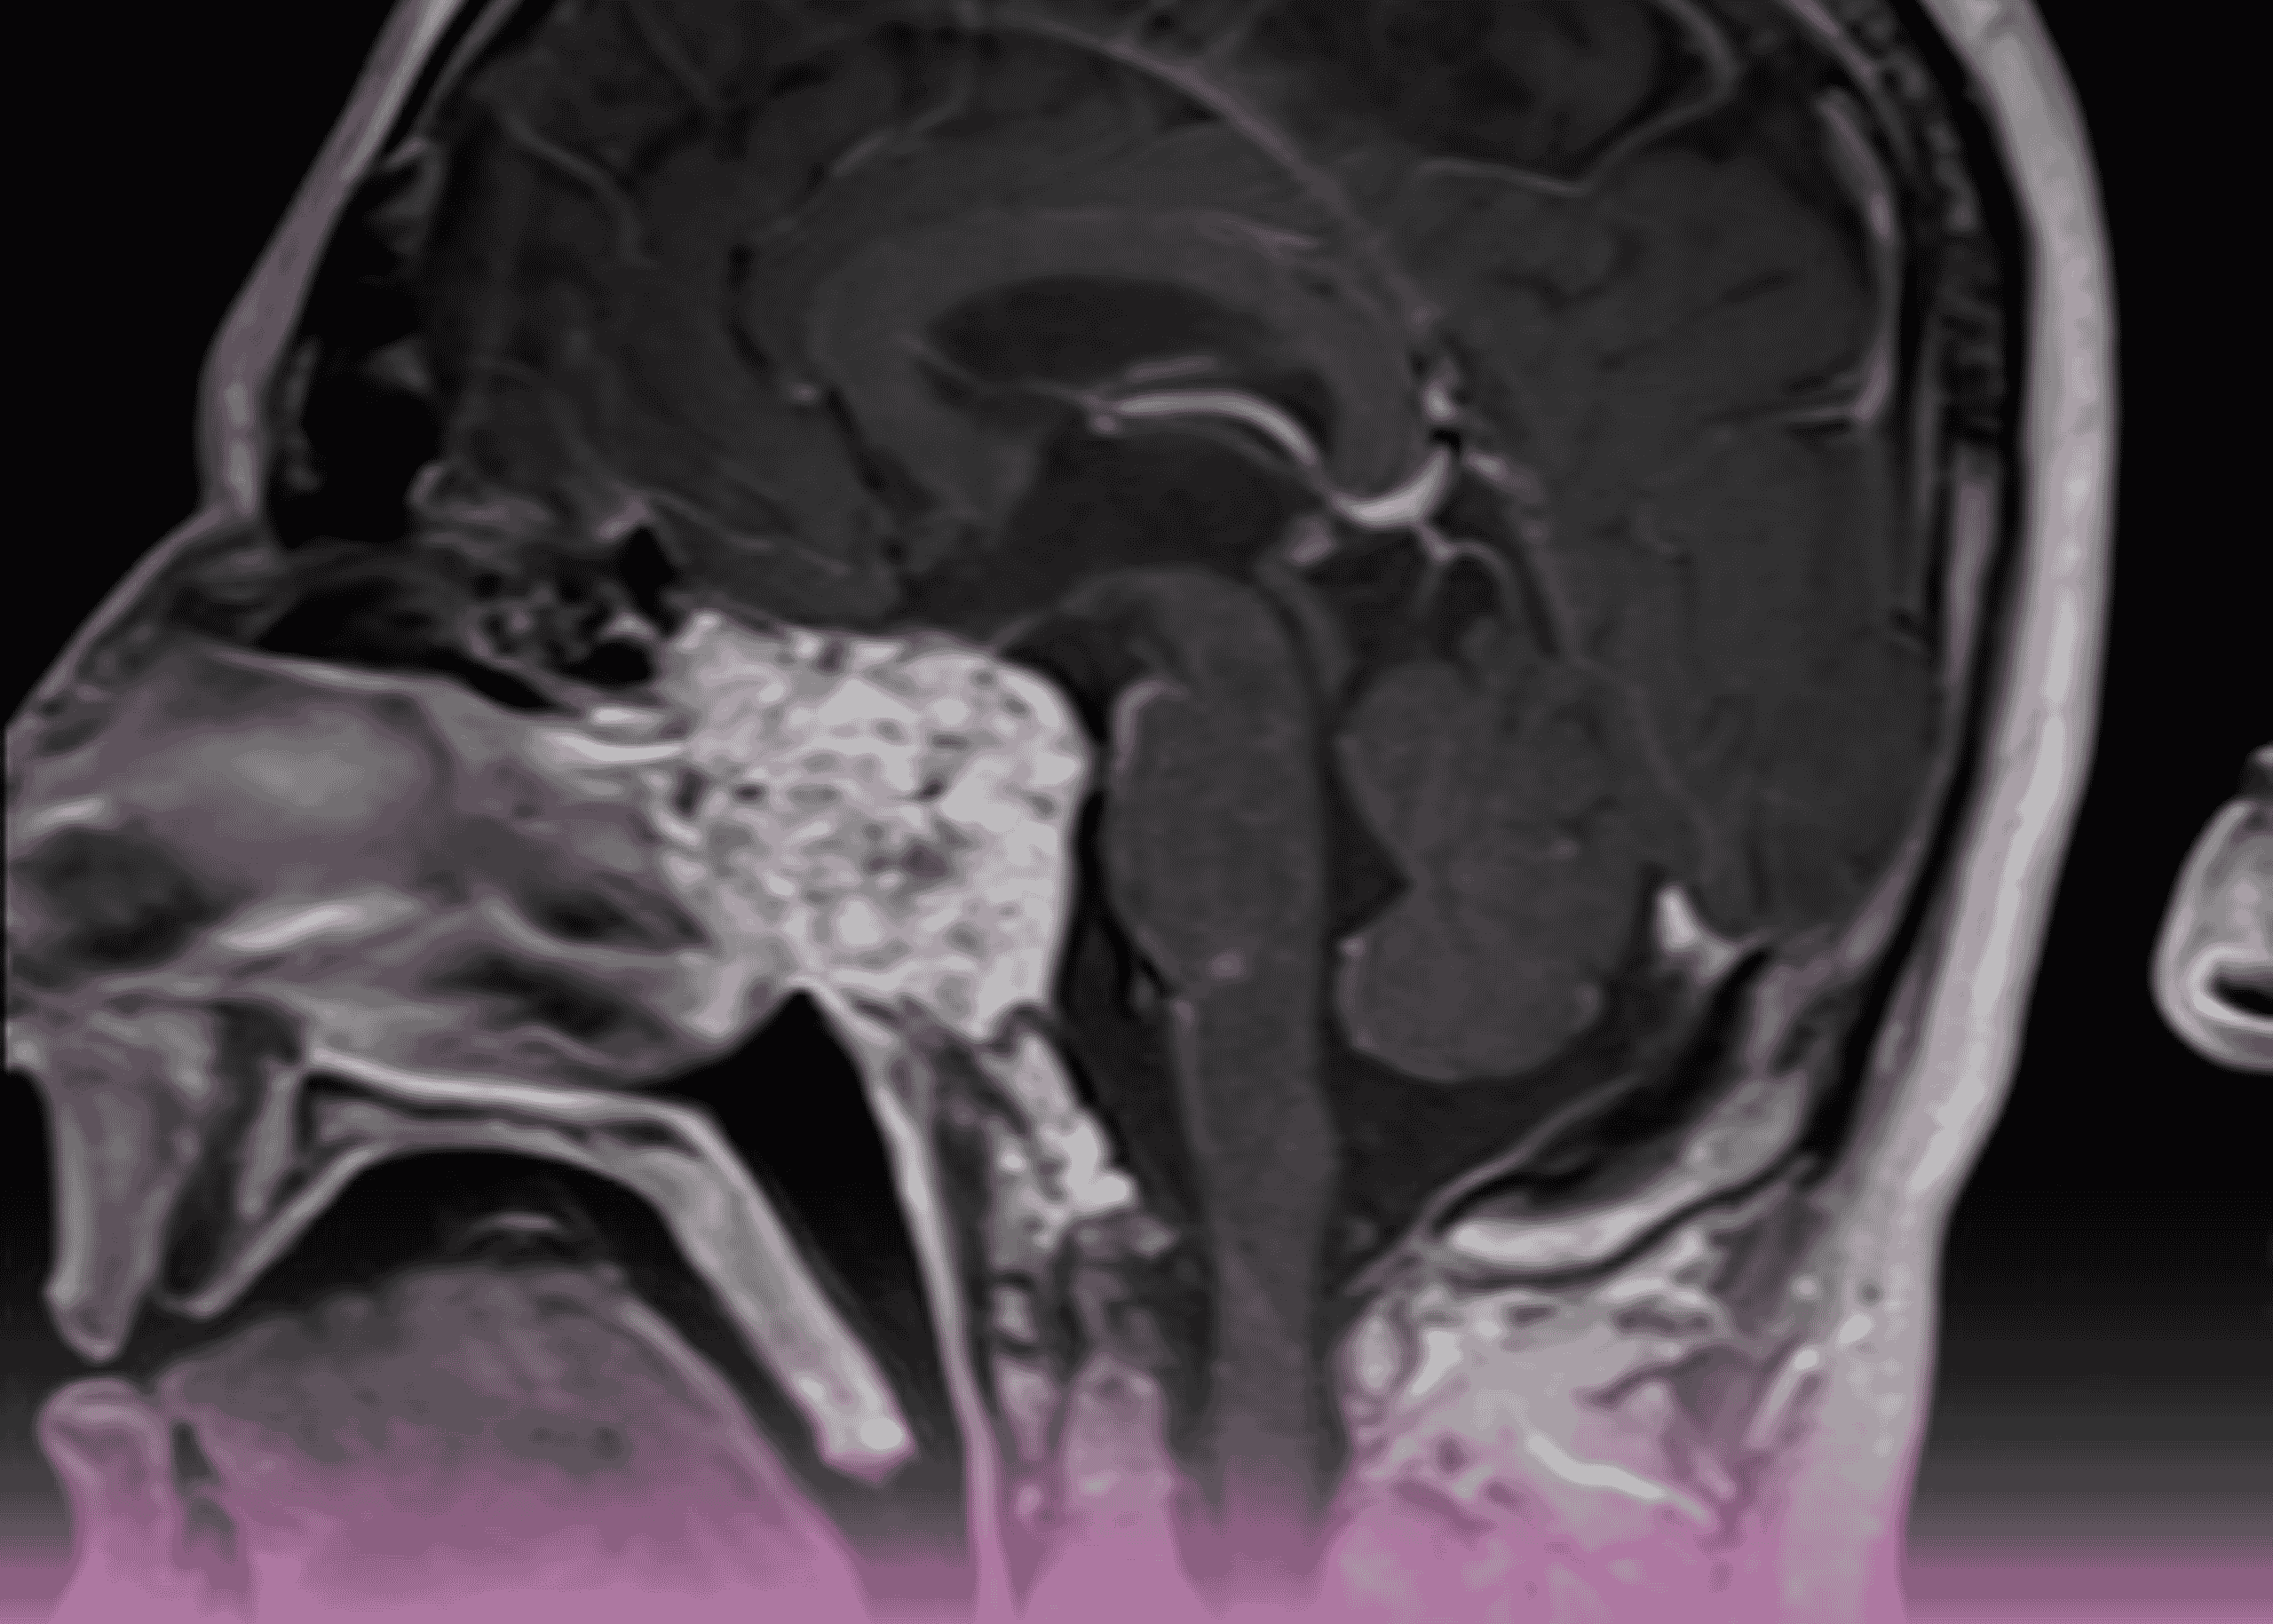

ورم كلايفال كوردوما: التدبير الجراحي المتقدم بالمنظار لورم نادر في قاعدة الجمجمة

مقدمة أورام قاعدة الجمجمة تمثل بعضاً من أكثر الحالات تحدياً في جراحة